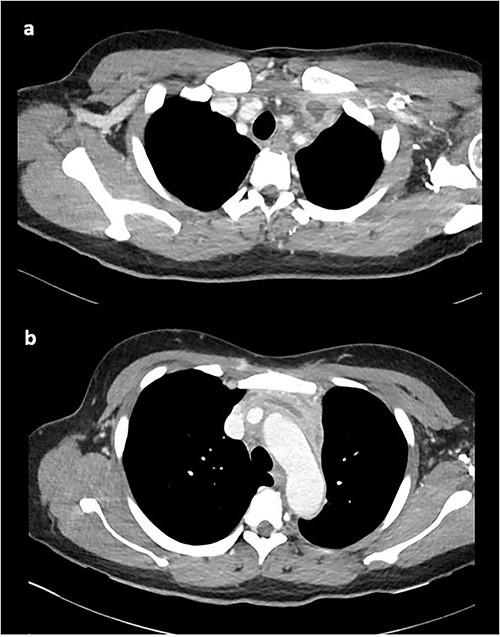

At this time, the mass was suspicious for a malignancy, possibly a thymoma, lymphoma or germ cell tumour. All serum tumour markers (AFP, CEA, CA19-9, CA125) were negative. FDG-PET demonstrated that the anterior mediastinal density had moderate FDG update and no other avid lesions elsewhere. After multidisciplinary discussion, the mediastinal density was thought to most likely represent left brachiocephalic venous thrombophlebitis. A dedicated computed tomography (CT) venogram was performed, demonstrating extensive UEDVT from the left internal jugular vein extending into the left brachiocephalic and subclavian veins, seen in Fig. 3.

CT venogram demonstrating UEDVT in left brachiocephalic vein in the (a) upper chest and (b) lower chest.

On direct questioning, the patient recalled extensive upper arm activity preceding the chest pain. She was diagnosed with primary UEDVT and started on an oral anticoagulant (apixaban 10 mg twice daily for 1 week and 5 mg twice daily ongoing) and discharged home with oral antihypertensives. Thrombophilia screen was negative (protein C, protein S, antithrombin III, beta 2 glycoprotein antibody, cardiolipin antibody, lupus screen, prothrombin gene mutation, factor V Leiden).